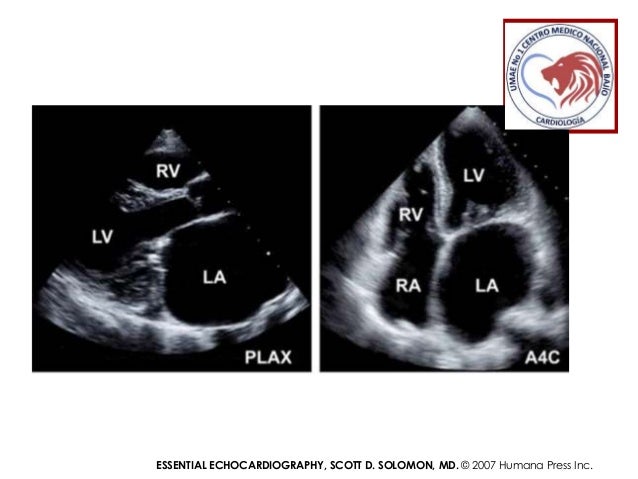

Ecocardiografia Valvulas Que Estudiamos En La Estenosis Mitral - Estenosis mitral significa que la valvula no se puede abrir lo suficiente.

Original Resolution: 638x479 px

Estenosis Mitral Ecocardiografia - Evaluacion de la estenosis mitral.

Estenosis Mitral Ecocardiografia - La estenosis mitral consiste en una reduccion del orificio valvular mitral por debajo de 2cm2☤, lo cual supone una obstruccion del flujo de entrada del ventriculo izquierdo.